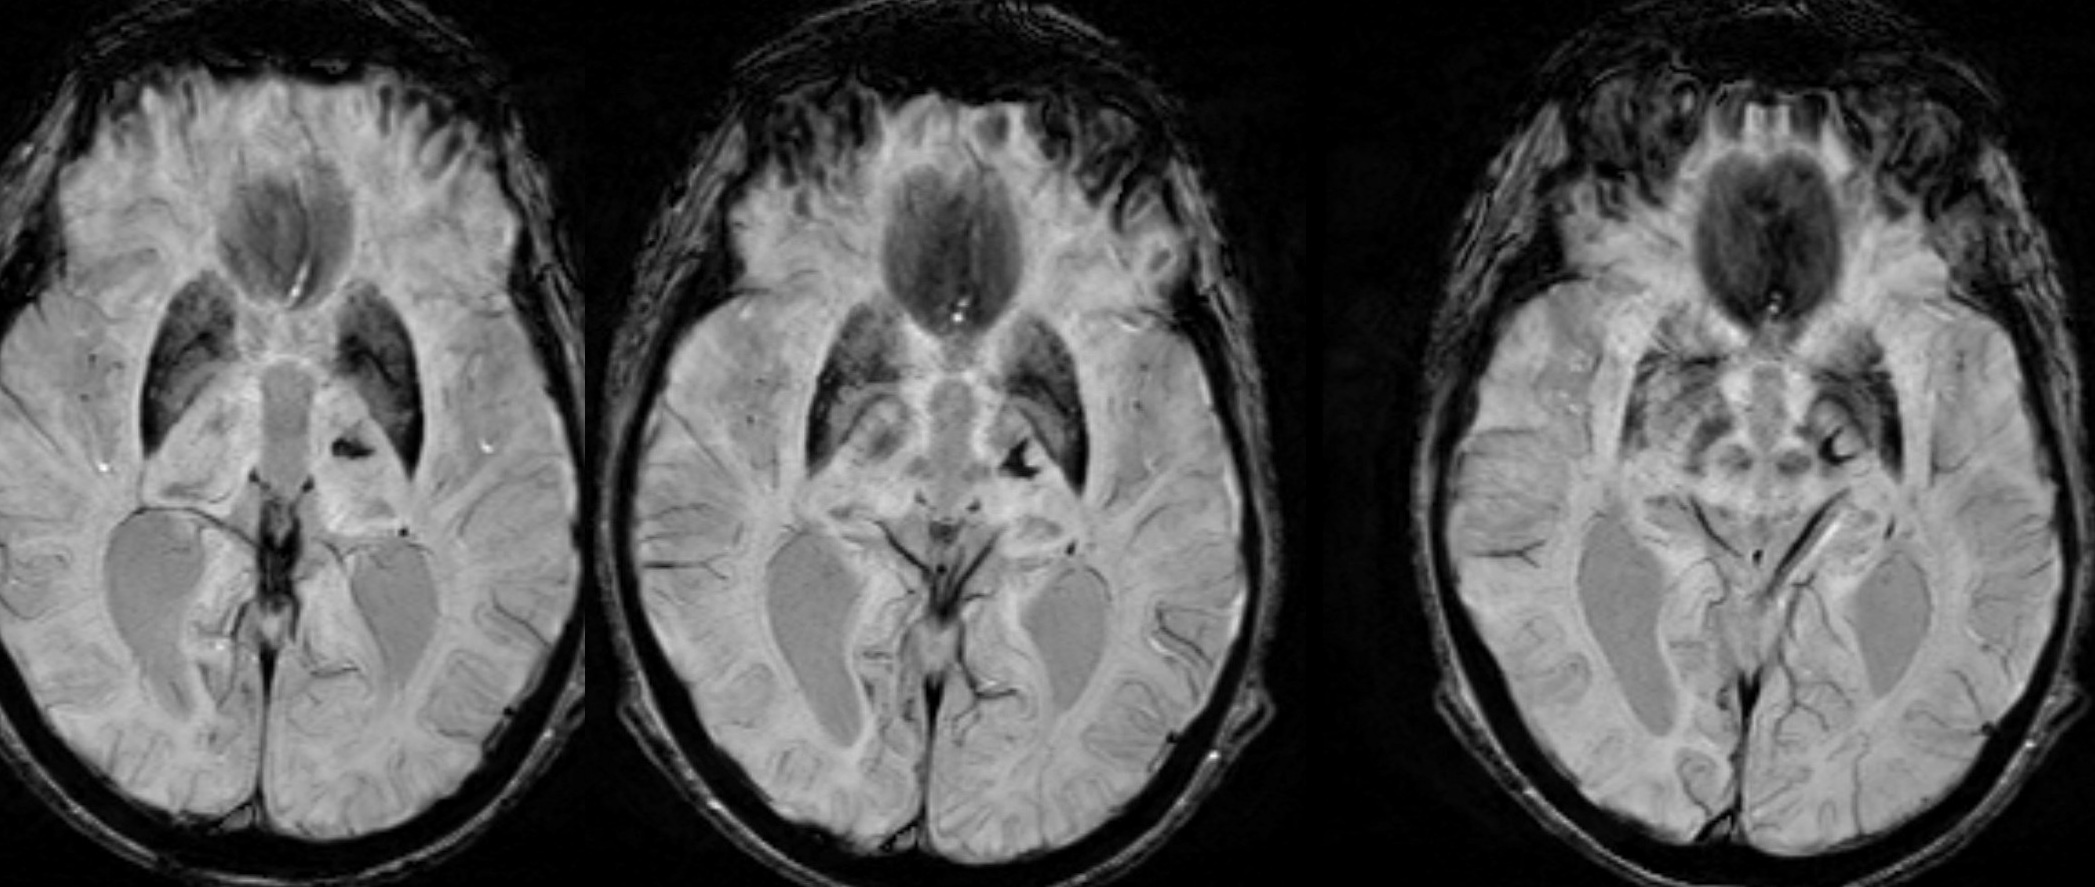

However, she developed high-amplitude right arm greater than leg movements in conjunction with a fall three weeks post procedure. A repeat MRI at three months showed new susceptibility within the left VIM lesion indicative of micro hemorrhage extending laterally toward the posterior limb of the left internal capsule and inferiorly toward the midbrain [Figure 1]. Multiple pharmacologic agents, including amantadine, propranolol, and VMAT-2 inhibitors, were ineffective or poorly tolerated.

Figure 1: Axial MRI SWI sequence